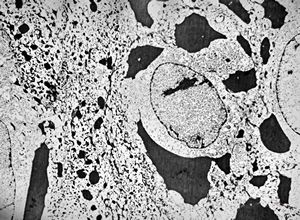

M, 60y. | otitis externa … microbes (fungi?) on the epidermal surface

M, 60y. | otitis externa … microbes (fungi?) on the epidermal surface